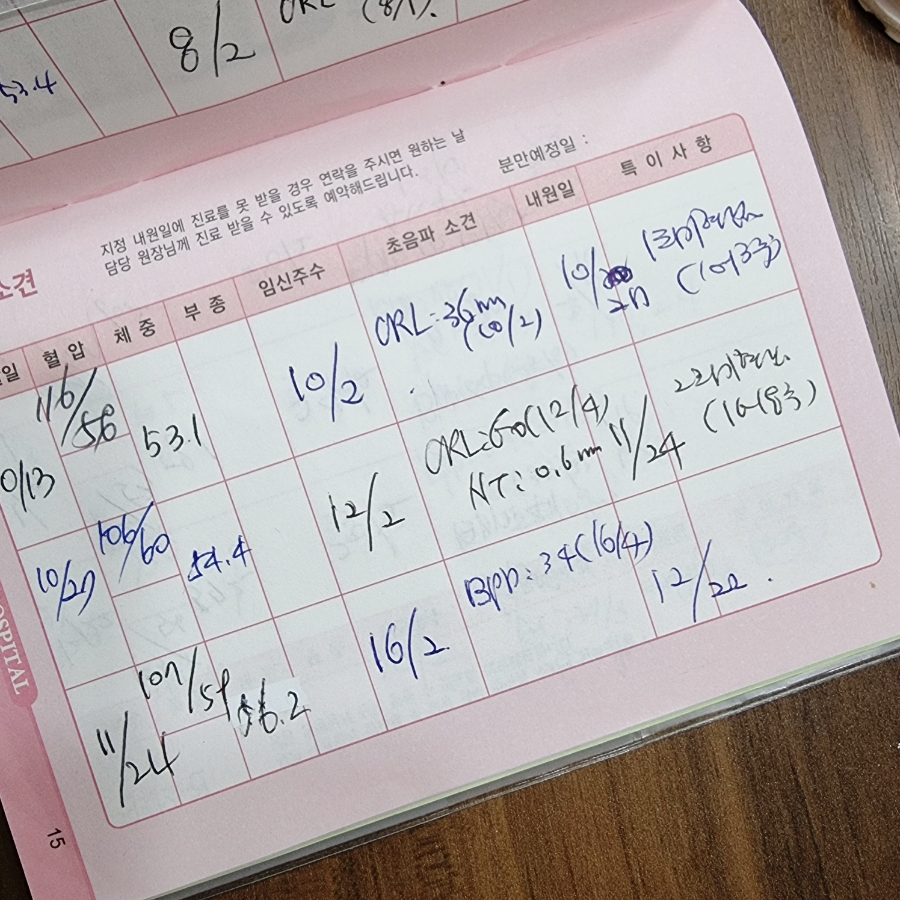

임신 4개월 12주차 초음파 사진입니다.머리의 몸체와 손발이 보이고 손톱이나 손톱도 자라는 시기입니다.심장박동음은 정상! 태아는 원래 심장이 빨리 뛰는게 정상입니다:) 제대가 정상적인 상태인지도 알 수 있습니다.

CRL: 태아의 머리에서 엉덩이까지의 길이, 태아의 크기는 6.2cm로 주수는 12주에 4일 정도, 민낯은 정말 평균 주수대로 커졌습니다.예정일은 5월 7일이라고 적혀있고 실제로 생얼은 1박 2일 유도분만 하고 5월 12일에 태어났습니다.

임신 11주 12주의 초음파 사진인데, 무엇을 찍었는지 잘 모르겠습니다.머리 같기도 하고 배 같기도 하고, 어쨌든 우리의 민낯 목둘레는 3mm 미만이고 목둘레 길이도 정상이라고 하더군요!

1차 기형아 검사 시기 비용

1차 기형아 검사 시기는 임신 10주에서 13주 사이에 이루어졌고, 저는 임신 12주에 검사를 했습니다.두 번째는 임신 중기의 15주~20주 사이에 실시합니다.결과는 2차 검사까지 모두 완료한 후 1차 2차 검사 결과를 합쳐서 최종 결과가 나옵니다.

1차 임신 기형아 검사 비용은 1,23500원이었습니다.혈액 검사와 초음파 검사까지 합쳐서 12만원대가 나온 것 같습니다.저는 고위험 산모와 병원에도 자주 가는 약주사약이 많아서 ㅠㅠ다른 사람의 출산 전까지 쓴다는 임신출산 바우처를 12주에 다 써버렸네요……잔액 0원..^^ㅋㅋㅋㅋ병원비는 정말 남들보다 5배는 쓴 것 같아서…